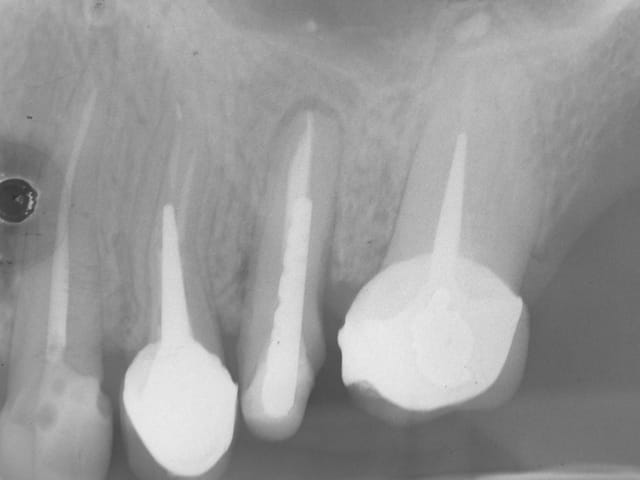

ci joint la radio de controle de l extraction reimplantation du cas de la page 11.

la reconstruction osseuse a l apex est evidente .

il n y a pas eu de provisoire sur cette dent et c est dommage .en effet il y a une migration en mesial et le ligament est lache .

faudrait faire la prothese au plus vite mais là c est une autre histoire.......financiere....

Radio de contrôle today de la latérale,

pour souvenir cette latérale a nécrosé ,

je l ai enlevé puis remis sans endo en novembre 2013

l endo a été faite 3 mois plus tard et la ceram aussi .

ça vous va comme ça ?